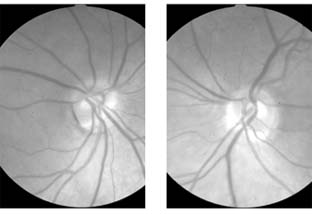

Optic neuritis may be due to a variety of causes (Table 14-1) but the most common is demyelination. Retrobulbar neuritis is an optic neuritis that occurs far enough behind the optic disk that the disk remains normal during the acute episode. Papillitis is disk swelling caused by inflammation at the nerve head (intraocular optic nerve) (Figure 14-8). Loss of vision is the cardinal symptom of optic neuritis and is particularly useful in differentiating papillitis from papilledema, which it may resemble on ophthalmoscopic examination.

Figure 14-8

Figure 14-8: Mild disk swelling in demyelinative papillitis, with disk leakage on fluorescein angiography.

Papillitis needs to be differentiated from pap-illedema (Figure 14-9). In papilledema there is often greater elevation of the optic nerve head, nearly normal visual acuity, normal pupillary response to light, associated intracranial pressure, and an intact visual field except for an enlarged blind spot. If there has been acute papilledema with vascular decompensation (ie, hemorrhages and cotton-wool spots) or chronic papilledema with secondary ischemia of the optic nerve, visual field defects can include nasal nerve fiber bundle defects and nasal quadrantanopias. Papilledema is usually bilateral, whereas papillitis is usually unilateral. Despite these obvious differences, differential diagnosis can be difficult because of the similarity of the ophthalmoscopic findings and because papilledema can be quite asymmetric and papillitis bilateral in some postviral events (eg, Devic's disease, or neuromyelitis optica; see below).

Figure 14-9

Figure 14-9: Mild papilledema. The disk margins are blurred superiorly and inferiorly by the thickened layer of nerve fibers entering the disk.